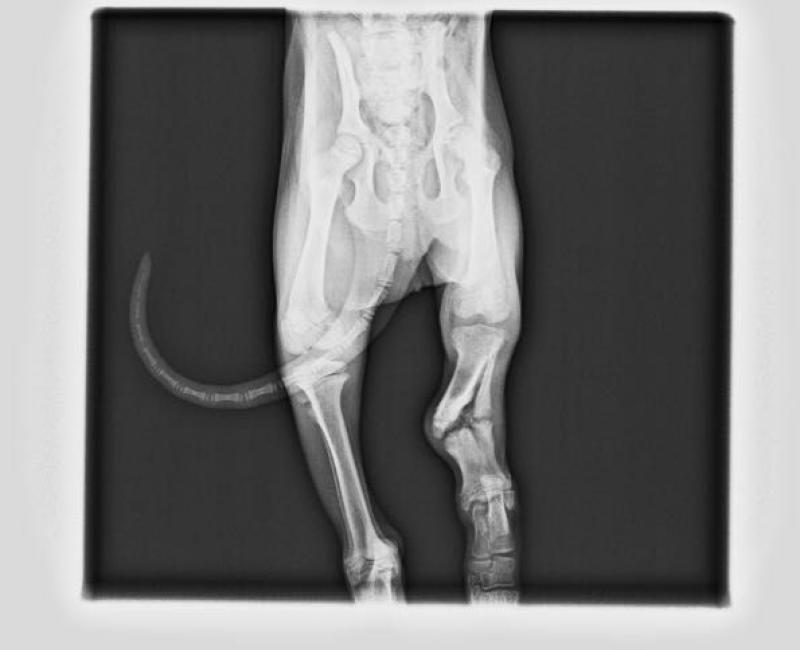

Jon adoptado!, nuestro pequeño Jon ha encontrado una familia que le trate como se merece. Gracias!.

Junio de 2017.